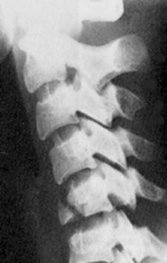

Flexion Tear Drop Fracture

The flexion tear drop fracture represents the most severe injury of the cervical spine. It results from severe flexion force (head-on collisions in motor vehicles) and often presents with quadriplegia and loss of anterior column sensation. The involved vertebral body is posteriorly distracted relative to the teardrop fragment which remains attached to the anterior longitudinal ligament. The facets are usually subluxed, resulting in compression upon the spinal cord and severe neurologic injury.

- Click on the image for a larger versionALateral radiograph of the cervical spine. This demonstrates the typical appearance of the flexion tear drop fracture of the C5 vertebral body. Copyright and courtesy of www.regionsem.org.